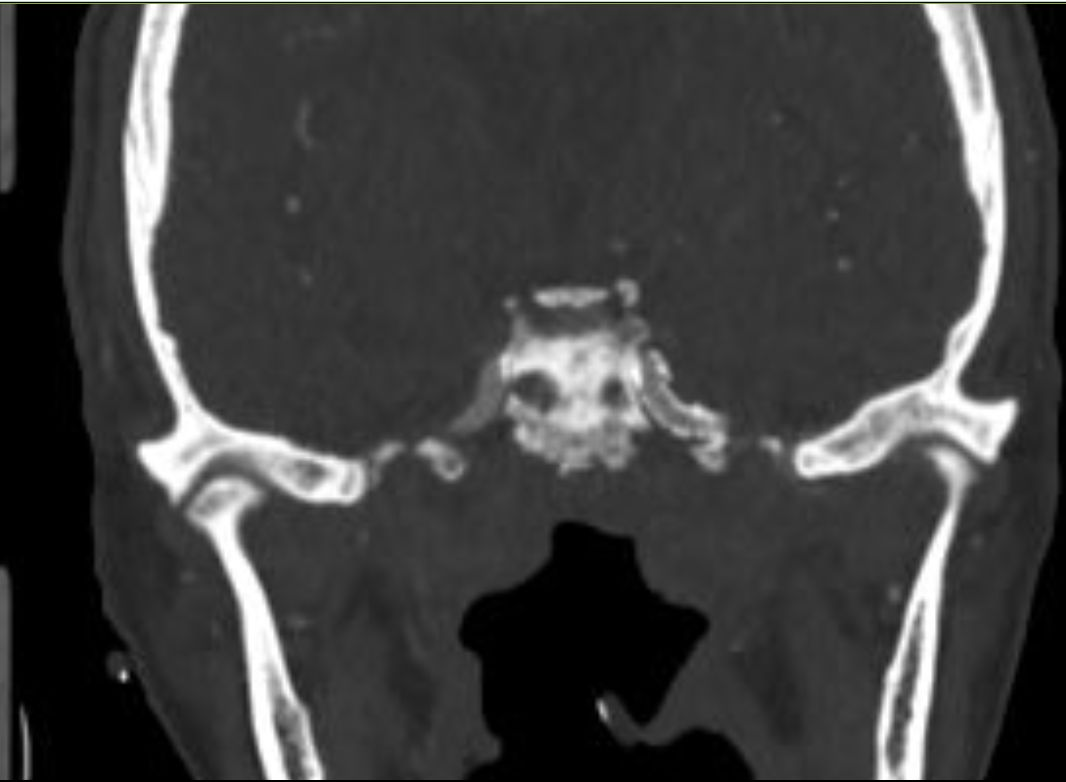

CTA:双侧岩骨、斜坡、翼突骨质破坏